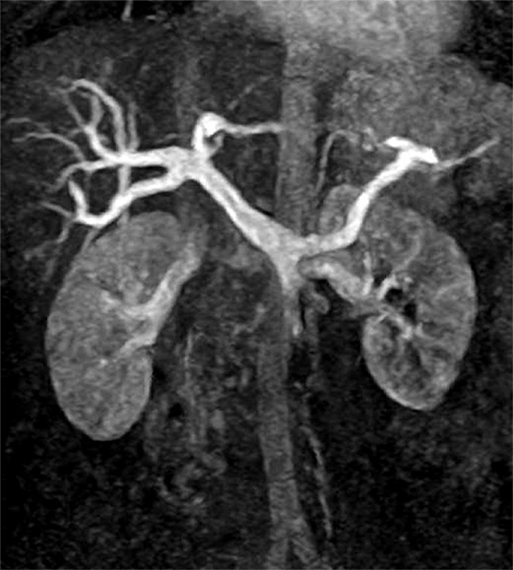

MR angiography

Maximum intensity projection(MIP)法による。門脈および脾静脈が描出されている。